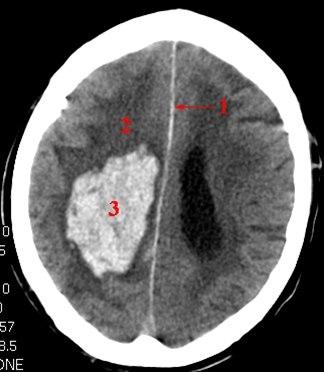

CT-bilde av hjerneblødning

CT av hjernen betegnes på fagspråket for cerebral CT. Bildene som tas brukes til å fremstille hjernevev, hinner og blodårer inne i hodet. Bløtvev med ulik tetthet kan skilles fra hverandre, og i hjernen kan f. eks. hjernebark og hjernemarg (grå og hvit substans) skilles fra ryggmargsvæsken. CT er godt egnet til å vise f.eks. akutte blødninger i hjernen, men når man skal vurdere hjernevev er MR en langt mer detaljert undersøkelse.

Bildene vises i ulike gråtoner. Jo lysere skygge, jo høyere tetthet har vevet eller strukturen. Bein blir hvitt, mens luft blir svart. Tilførsel av røntgenkontrast via blodet kan gi bedre bildeinformasjon, f.eks lar store blodårer seg lettere fremstille etter tilførsel av kontrast i årene.

CT utføres ved mistanke om sykdom eller forandringer i hjernen. Særlig gjelder det i utredningen av akutt tilfeller hvor man mistenker blødning, f.eks. slagtilfeller. CT kan også være første ledd i utredningen av uklare hodeplager, som f.eks. langvarig hodepine.

Hjerneblødninger kan være vanskeligere å se, særlig dersom det er gått noe tid (dager, uker) siden blødningen skjedde. En blodpropp i hjernen (lager et hjerneinfarkt) kan overses dersom det har gått for kort tid, dvs. få timer siden skaden skjedde. Pasientbevegelser reduserer kvaliteten på bildene.

Hva kan man finne?

En lang rekke forandringer i hjernen kan påvises ved CT. De hyppigste sykdommene man kan finne er hjerneblødninger og skader på skallen, hjerneskader som følge av hjerneslag (blødning eller blodpropp, trombose), svulster, spredning fra kreftsykdom annet sted i kroppen, betennelser og demensforandringer.